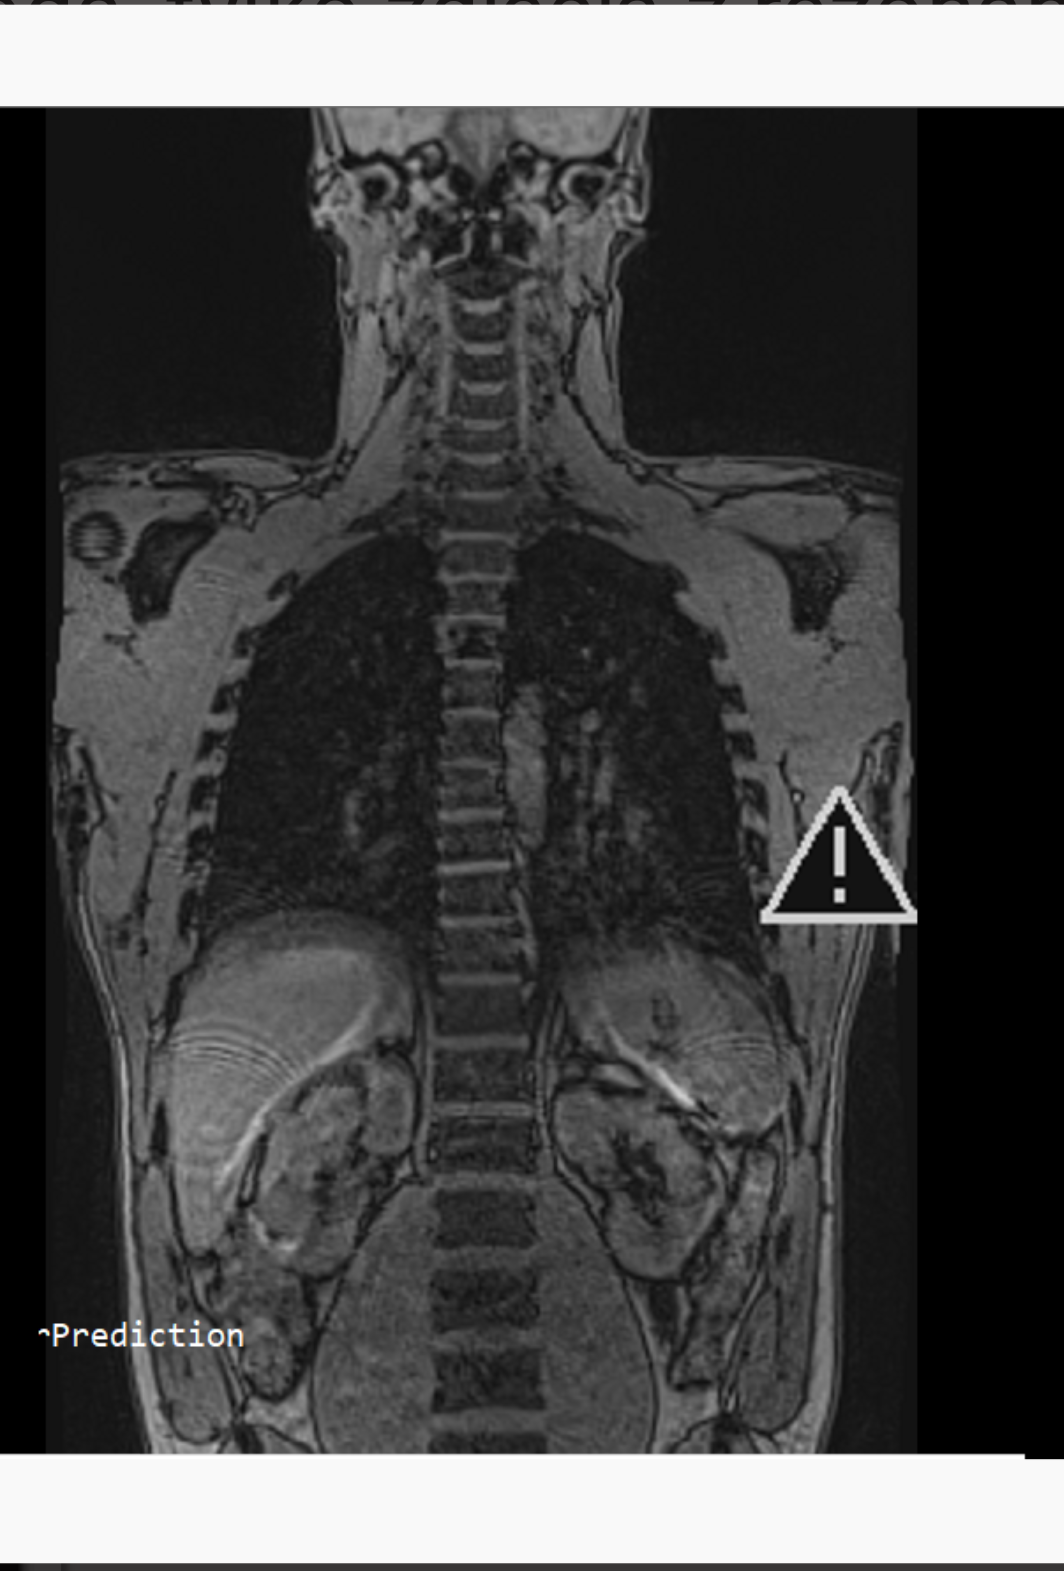

Witam, byłem dziś na usg w celu znalezienia przyczyny przewlekłego bólu pleców w odcinku piersiowym (promieniowanie do szyi i głowy). Nie mam opisu wykonanego przez lekarza radiologa, tylko zdjęcia z rezonansu w związku z tym mam pytanie, co może być na dołączonym przeze mnie zdjęciu. Ból odczuwam właśnie w okolicach białego "kształtu".Widzę jakby nacisk na kręgosłup. Czy ktoś może mi powiedzieć czym jest ten "twór" Pragnę powiedzieć, że z tym bólem męczę się od 7 lat, okresowo do mnie wraca.